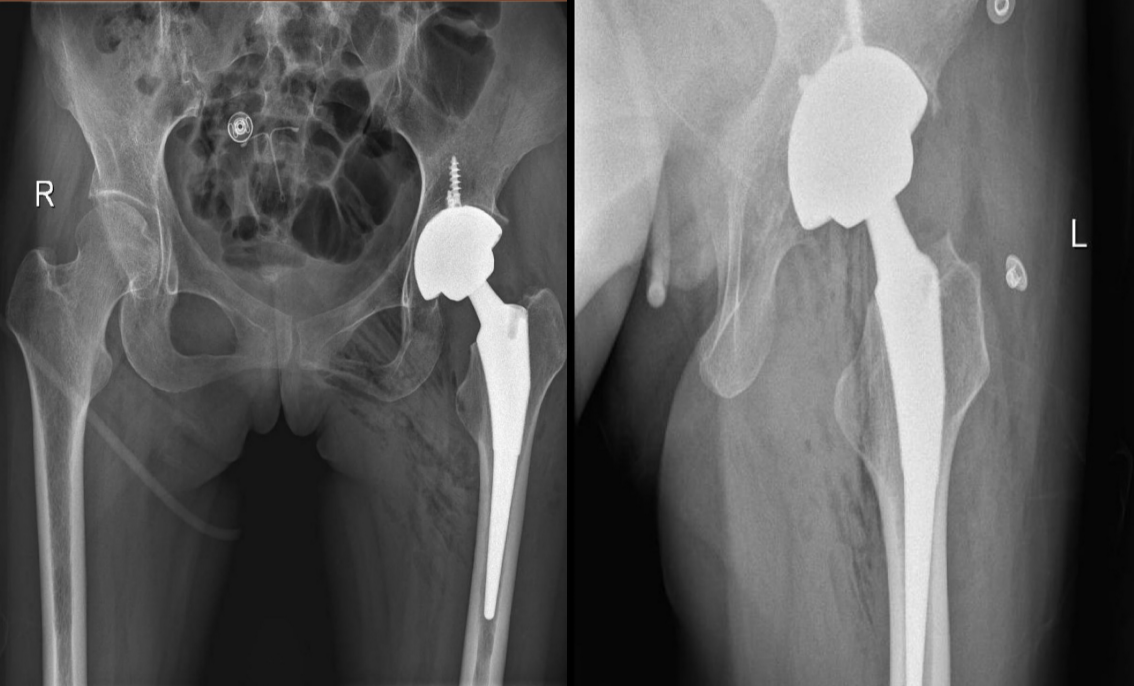

经过严格规范的药物治疗后效果欠佳,且患者出现关节畸形,严重影响关节功能的情况,可考虑手术治疗,手术治疗具有矫正畸形、恢复关节功能的作用。手术方式包括:关节镜下手术、关节置换术等。